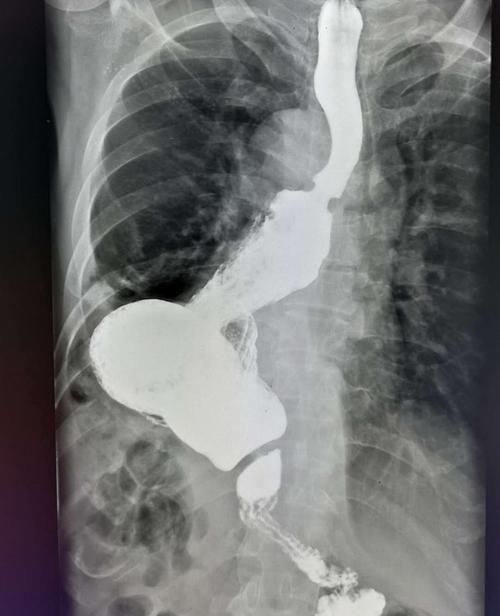

文章插图

比如这位食道癌患者,因为吞咽困难伴有体重下降入院,手术切除肿瘤、解除梗阻,拆线后食欲恢复,体重逐步增加,好现象!